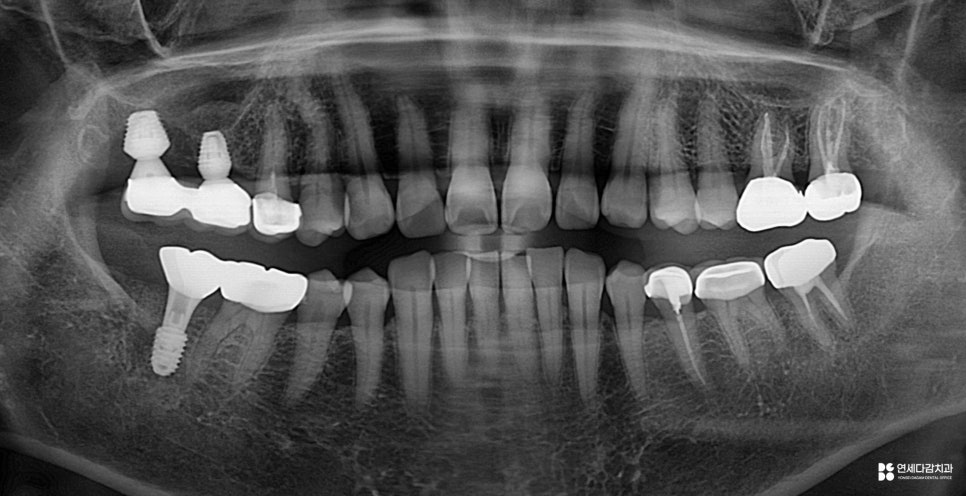

위아래 병변의 진행 정도를 살펴봤을 때,

47번은 이미 치근 부위로 확산되어 있습니다.

치근은 치조골 속에 위치하고 있어

병변에 접근하는 것이 매우 어렵습니다.

또한 치근이 손상되면 강도 자체가 저하되어,

저작압을 버티기 어려운 상태가 됩니다.

기능 회복을 위해 임플란트를 심은 모습입니다.

위와 같이 엑스레이에서도

병변이 명확히 확인할 수 있는 반면,

실제로 병변을 정리해 보기 전까지는

정확히 알 수 없는 부분도 존재합니다.

개롱역 치과 에서 설명해 드리는

대표적인 것이 신경 침범 여부입니다.

방사선 사진상으로

치수 근처까지 도달한 것처럼 보이더라도,

실제로 치수까지 이어졌는지는

직접 제거해 보아야 알 수 있습니다.

46번이 그런 경우입니다.

초진 사진에는 내부 깊이 확산되었지만,

다행히 침범하지 않은 상황입니다.

이런 경우 크라운 치료를 진행하고,

경과를 지켜보게 됩니다.

반면 27번처럼

충치 제거 과정에서 치수 조직으로

우식이 이어진 것이 확인된다면

신경치료를 진행하게 됩니다.

이렇게 식립된 임플란트도 유착 기간을 거쳐

보철을 수복하면 마무리가 됩니다.

각각 부위마다 염증 소견은 없는 것으로 봐서,

상태는 양호한 것으로 평가됩니다.